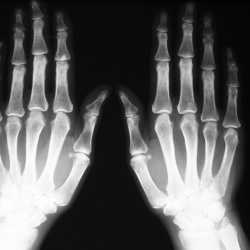

Пациентка 38 лет, жалобы на боли в суставах стоп и рук около 2 -х месяцев. Болезненность при пальпации поясничного отдела позвоночника.